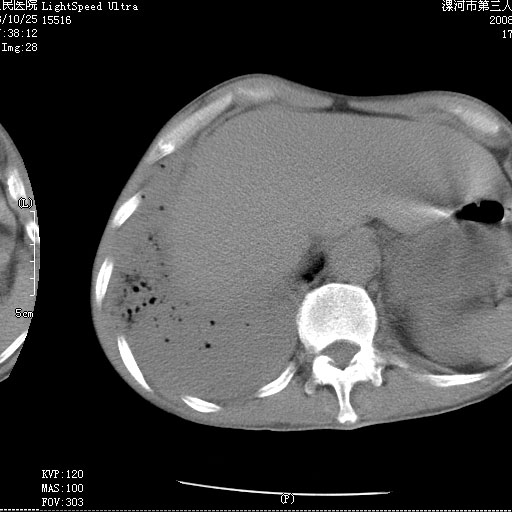

m 老年 发烧、呼吸困难,慢支、肺气肿多年;记的那次是下午大概17:38做的,晚上窒息死亡。

上面的层面就慢性支气管炎肺气肿、肺大泡,别的没有什么、也就不传了。

当时我怀疑:1、阻塞性肺不张早期 2、肺脓肿早期,望老师们发表意见

病灶边缘清---多个含气小腔---近端未见通畅气管影-----支持-----慢性肺脓肿继发阻塞性肺不张

阻塞性肺不张原因-----脓液未排出

1、右侧脓胸;2、copd;

3、细支气管肺泡癌可以排除,病变以斜裂为界,呈大片状高密度影,内可见多发小气泡,表明有产气杆菌感染所致,内无明显的支气管“枯树枝征”表现,再结合其临床改变(细支气管肺泡癌临表表现重、影像表现轻)所以不符合细支气管肺泡癌(炎症型)的改变。

病变按肺叶分布,病变内可见多个小空腔影,未见充气支气管影,中间段支气管管腔肺窗示密度欠均匀,下肺支气管分叉处基底段支气管隐约可见,未见明显狭窄,中叶支气管通畅,

考虑:阻塞性肺炎伴小脓肿形成可能性大。(痰栓可能性大)

右下肺实变,内有弥漫分面小气泡而无支气管征,叶间裂前移,呈臌大之形,而无收缩之状,兼纵隔稍左行移,故。不支持不张,倒支持大叶肺叶,如楼上所说,小气泡不象残留之肺,不可以考虑产气菌感染吗。

阻塞性肺炎,肺脓肿形成。依据,右下支气管不通,大片实变形内可见小气泡。不支持肺不张。